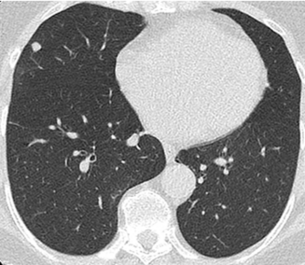

Beispielhafte Aufnahmen verschiedener Erkrankungen

(Lungenklinik Lostau)

Die High-Resolution-Computertomographie (HRCT) ist eine spezielle CT-Technik mit sehr hoher Detailauflösung. Sie ist besonders wichtig für die Diagnostik und Verlaufskontrolle interstitieller Lungenerkrankungen (ILD), da feine Muster im Lungengewebe differenziert beurteilbar werden.

Interstitielle Lungenerkrankungen (ILD) sind Erkrankungen, bei denen sich das Lungengewebe durch Entzündung oder Vernarbung verändert. Die High-Resolution-Computertomographie (HRCT) ist dabei ein zentrales Werkzeug, weil typische Muster in der Bildgebung wichtige Hinweise auf Ursache und Stadium geben.